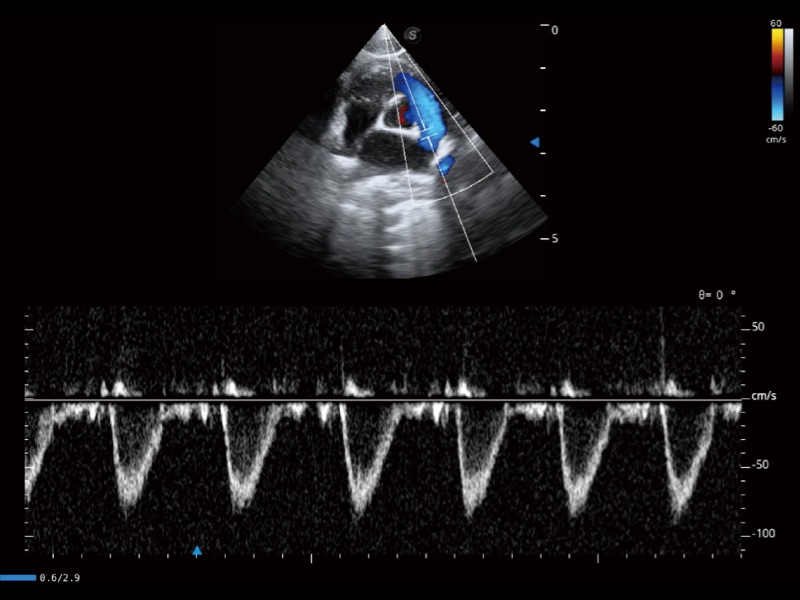

通过360度任意调节3条M型取样线,在同一心动周期上观察心脏不同位置的运动曲线,得到准确的心功能测量数据,有效评估心肌运动及左心室功能。

实时用颜色表示心肌组织运动,观察和定量组织的运动情况,对快速检测与评估心肌的灌注和活性、电传导及心肌收缩和舒张功能等均能提供重要的诊断信息。